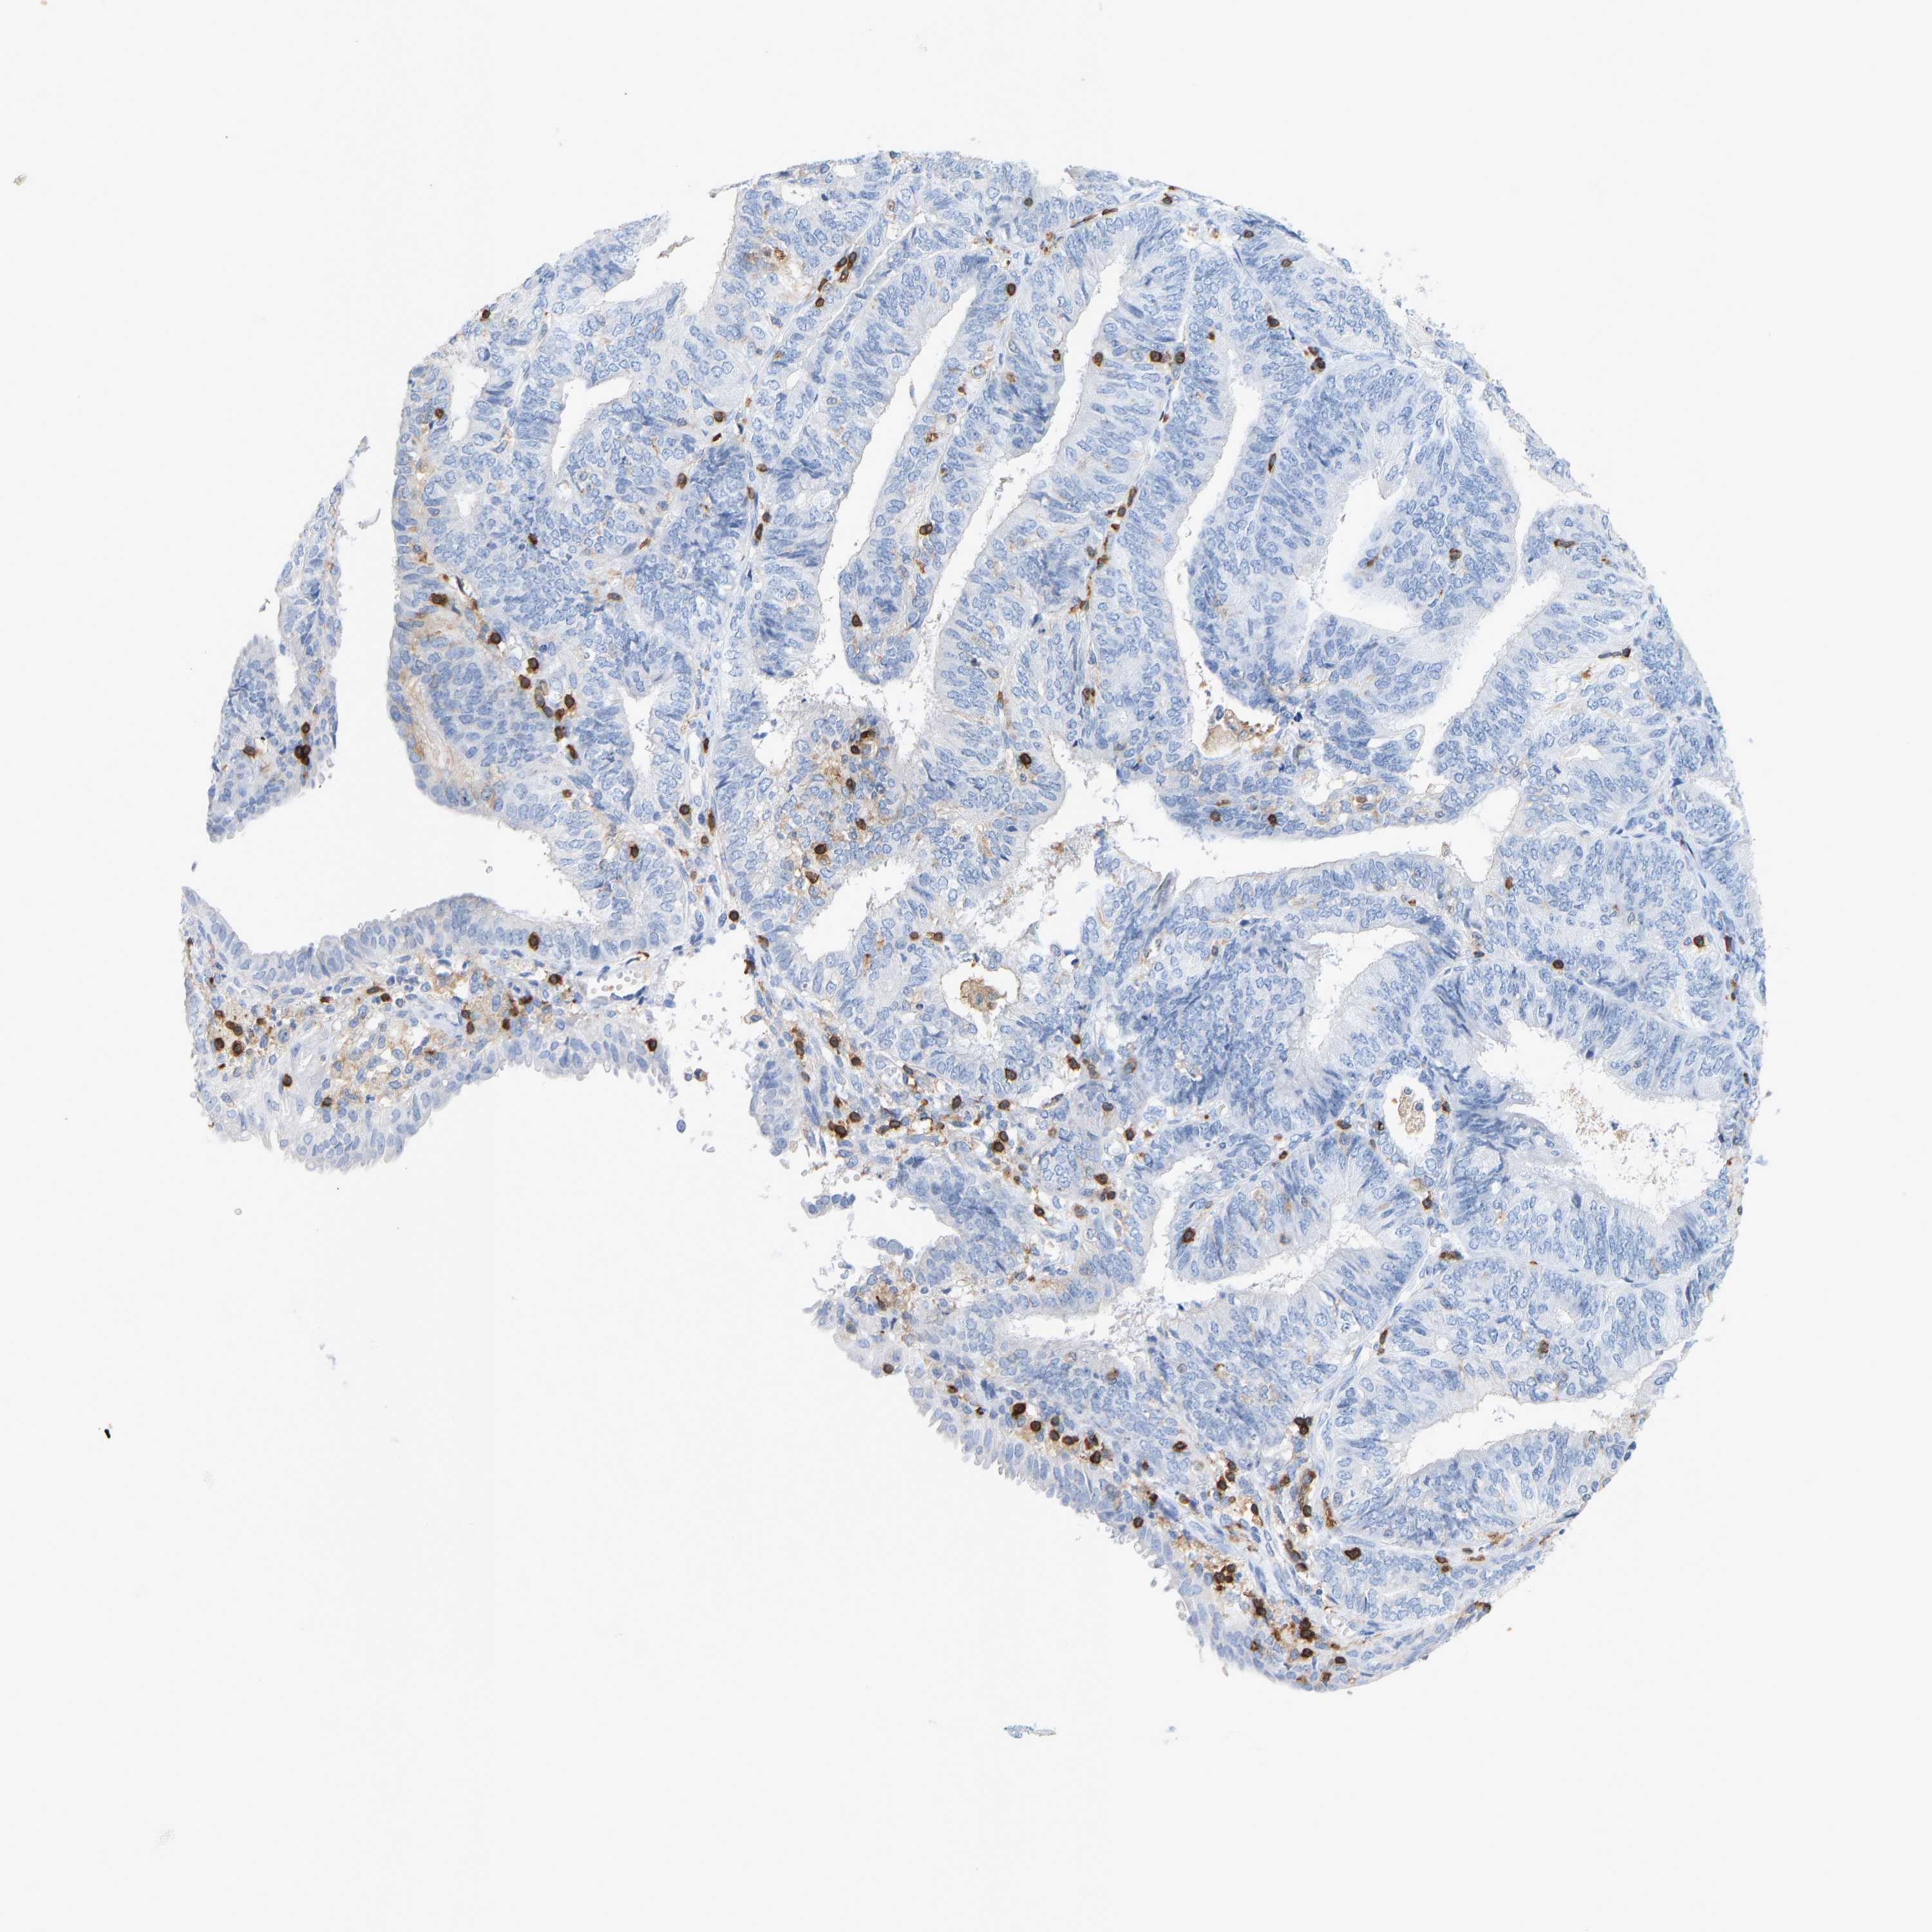

ENDOMETRIAL CANCER - Protein expressioni

A mouse-over function shows sample information and annotation data. Click on an image to view it in a full screen mode. Samples can be filtered based on level of antibody staining by selecting one or several of the following categories: high, medium, low and not detected. The assay and annotation is described here.

Note that samples used for immunohistochemistry by the Human Protein Atlas do not correspond to samples in the TCGA dataset.

Antibody stainingi

Antibody staining in the annotated cell types in the current human tissue is reported as not detected, low, medium, or high, based on conventional immunohistochemistry profiling in selected tissues. This score is based on the combination of the staining intensity and fraction of stained cells.

Each image is clickable and will lead to virtual microscopy that enables deeper exploration of all samples and also displays staining intensity scores, fraction scores and subcellular localization as well as patient and tissue information for each sample.

Antibody HPA018849

Antibody HPA019536

Antibody CAB033987

Staining

High

Medium

Low

Not detected

Intensity

Strong

Moderate

Weak

Negative

Quantity

>75%

75%-25%

<25%

None

Location

Nuclear

Cytoplasmic/membranous

Cytoplasmic/membranous,nuclear